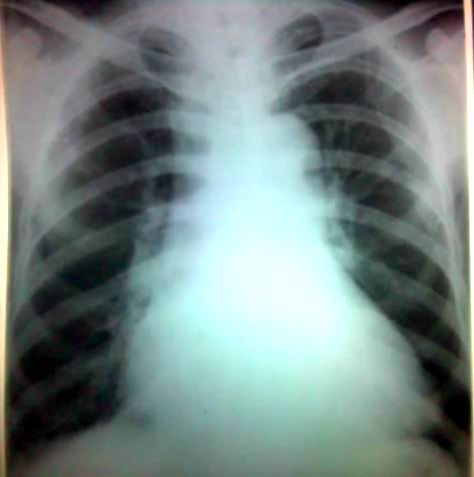

体俭发现心影增大

高心病.上腔v影增宽

考虑左心功能不全

体俭发现心影增大,平日无不适,询问病史全无,是这样吗?

请结合临床,平片未见明显异常,请测一下ctr.

心影增大,建议心脏超声